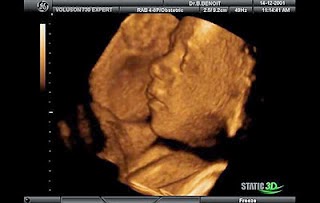

22 haftalık gebelik sürecinde bilinçli anne olarak kendinizi daha da geliştirmeniz ve bebeğiniz için daha neler yapabilirsiniz makalemizde anlattık. Boyu ise yaklaşık 19 20 santimetre civarındadır. çünkü sıvılar vücudunun besinleri işlemesine yeni hücreler oluşturmasına kan hacminin korunmasına ve vücut ısısının düzenlemesine yardımcı olur. 22 haftalık gebelikte bebeğin vücudu tüycüklerle kaplı olur.

Vücudunuz bebeğiniz için hazırlanmakta. Su su ve daha çok su. 22 haftalık gebeliklerde annelerde meydana gelen değişimler bütün anne adayları için merak konusu hamilelik artık eskisi kadar ağrılı ve şikayetli değil. Bu tüyler sonraki haftalarda dökülmeye başlayacak ve kalanı da doğumdan sonra kendiliğinden dökülecektir.

Gebelikte 22 hafta bebekteki değişiklikler.